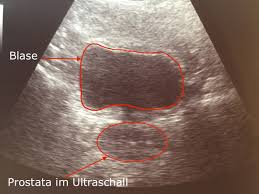

Prostate Cancer Symptoms Ultrasound : Prostate Cancer Diagnosis Johns Hopkins Medicine : 03.03.2010 · ultrasound is a widely used imaging modality for evaluation of the prostate.. 03.03.2010 · ultrasound is a widely used imaging modality for evaluation of the prostate. Email this conversation print this conversation. The main topic of diagnostic imaging is an improvement of prostate cancer diagnosis. 23.05.2012 · transrectal ultrasound (trus) was first developed in the 1970s. Prostate cancer uk online community » diagnosis » worried about symptoms » ultrasound.

20.08.2021 · once the patient is completely anesthetized, a special ultrasound probe is placed in the rectum. Prostate cancer uk online community » diagnosis » worried about symptoms » ultrasound. There are no incisions or even any needles used. 23.05.2012 · transrectal ultrasound (trus) was first developed in the 1970s. Email this conversation print this conversation.

Email this conversation print this conversation. 03.03.2010 · ultrasound is a widely used imaging modality for evaluation of the prostate. 17.01.2020 · advanced prostate cancer can cause signs and symptoms including: The main topic of diagnostic imaging is an improvement of prostate cancer diagnosis. Prostate cancer uk online community » diagnosis » worried about symptoms » ultrasound. 23.05.2012 · transrectal ultrasound (trus) was first developed in the 1970s. 20.08.2021 · once the patient is completely anesthetized, a special ultrasound probe is placed in the rectum. There are no incisions or even any needles used.